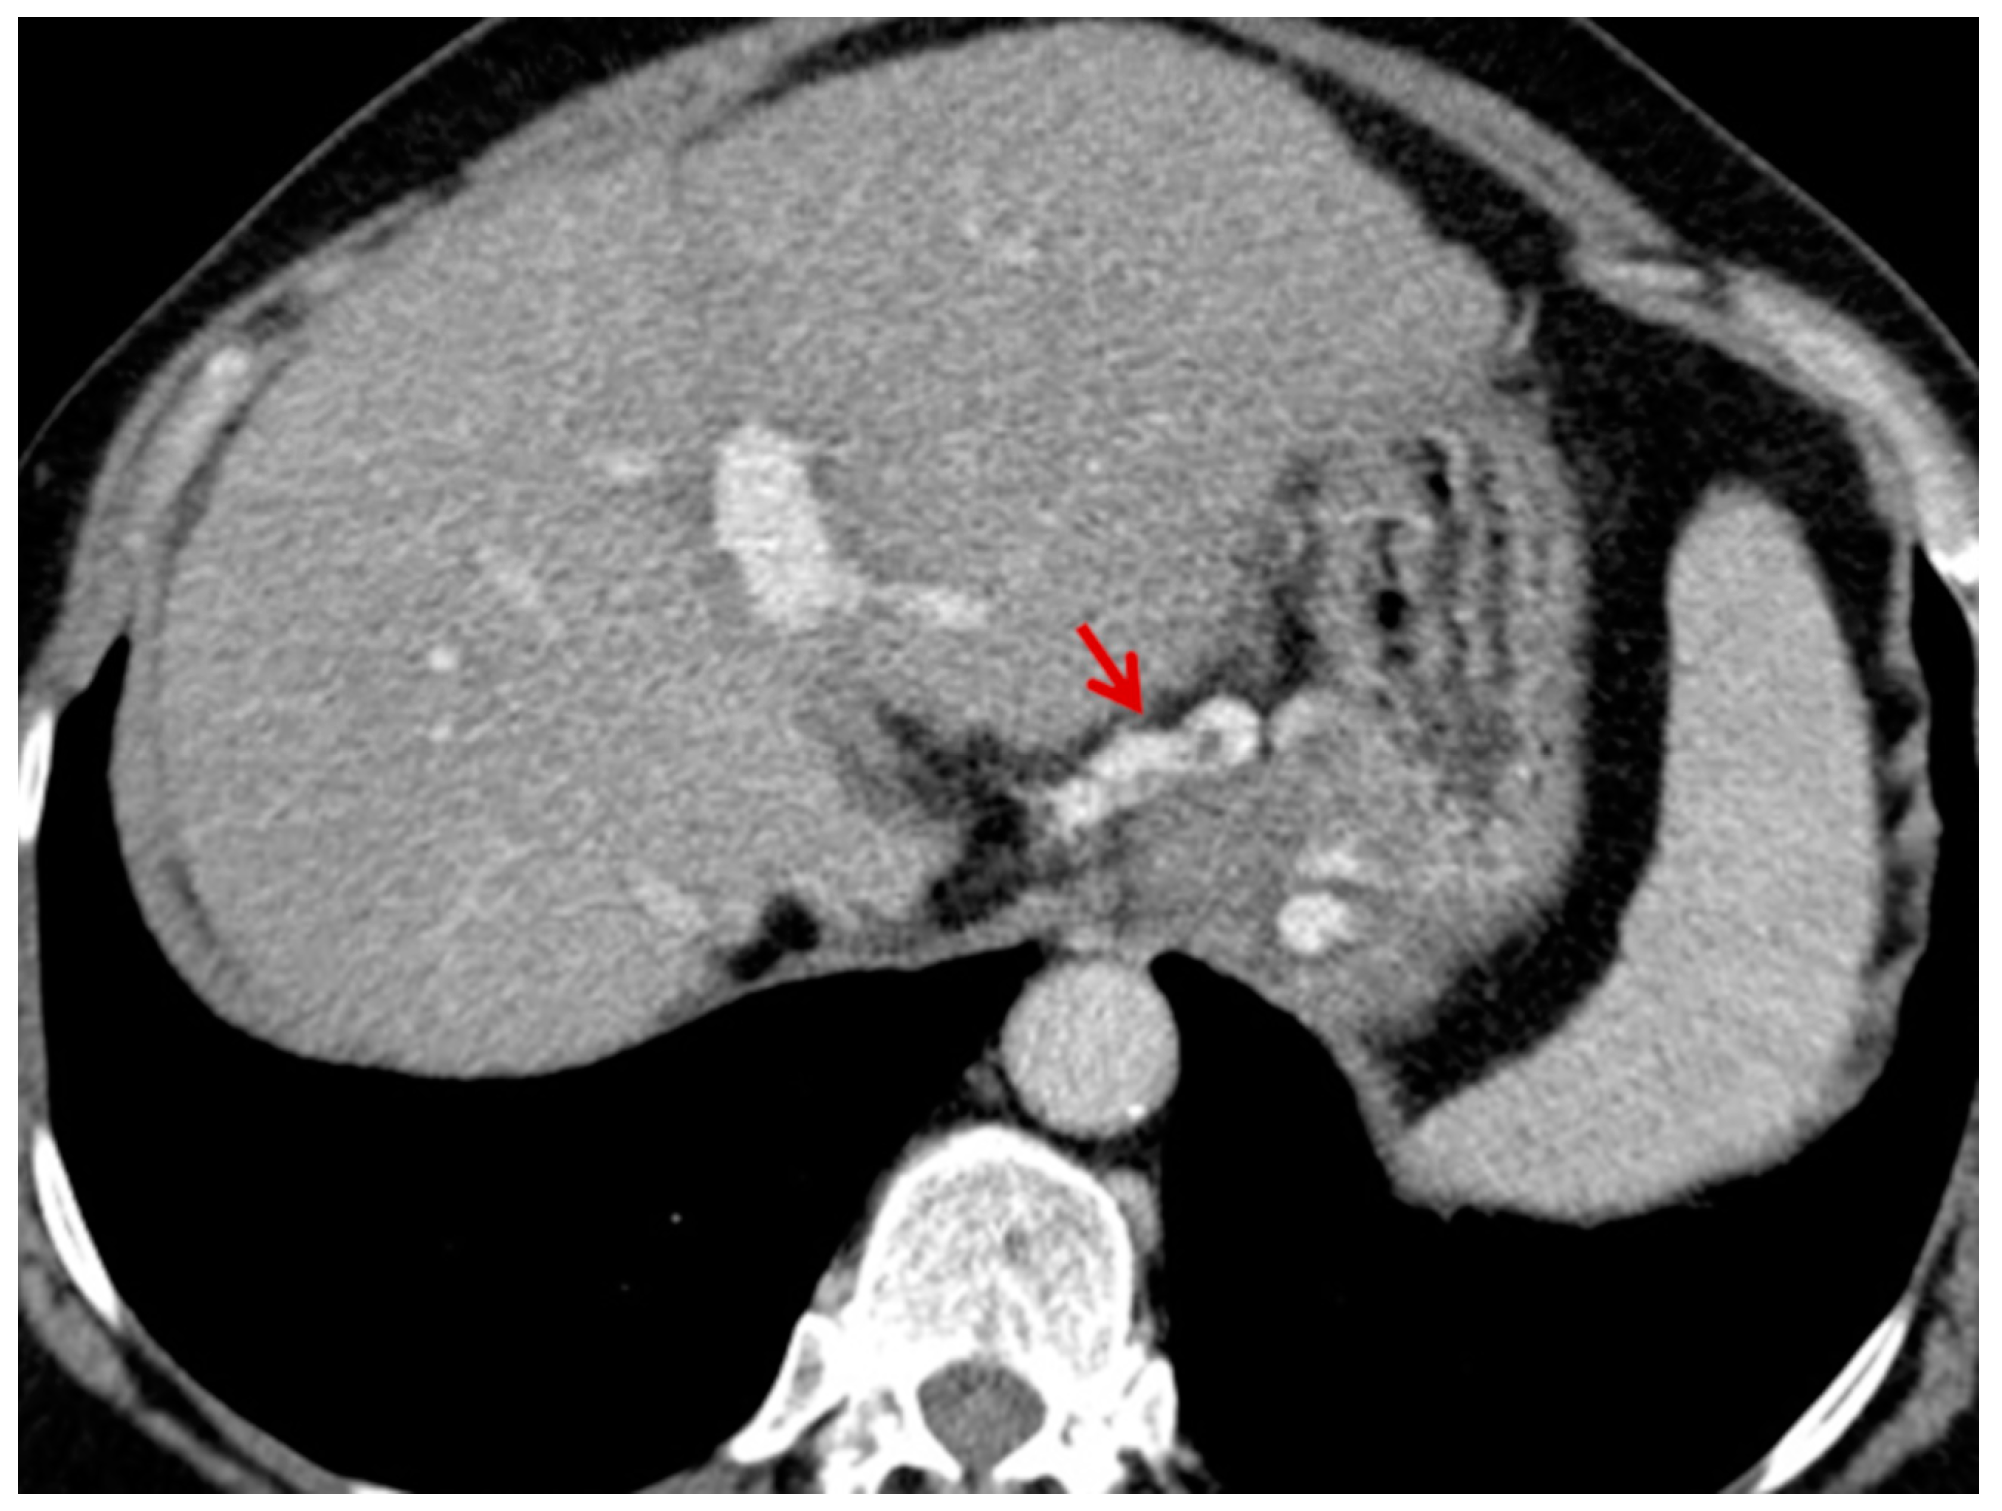

For this study, the images were retrospectively analyzed in consensus by two readers with experience in the field of abdominal imaging. The two readers assessed the following CT features: (1) The presence or absence of paraoesophageal varices and the size(mm) of the largest varix (Figure 1); (2) the presence or absence of paragastric varices and the size (mm) of the largest varix (Figure 2); (3) the largest diameter of the left gastric vein (Figure 3); (4) the presence or absence of splenorenal shunts and the size(mm) of the shunt (Figure 4); (5) the presence or absence of a repermeabilized round ligament and the size(mm) of it (Figure 5).

Figure 2. Axial contrast-enhanced CT shows enlarged paragastric varices (red arrow).